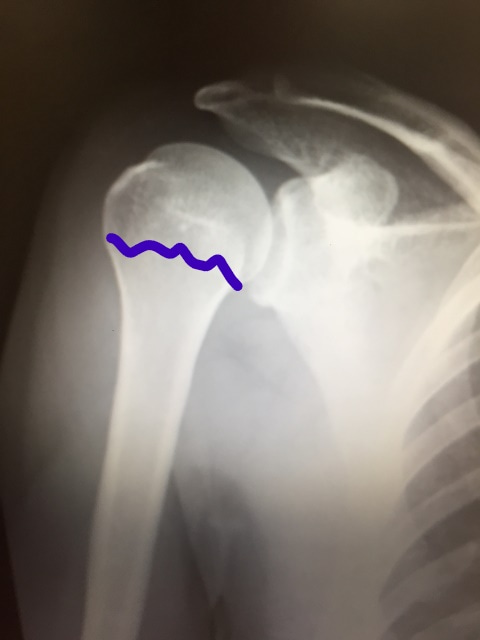

野球肩

・腱板損傷

・インピンジメント症候群

・関節唇損傷

・リトルリーガーズショルダー